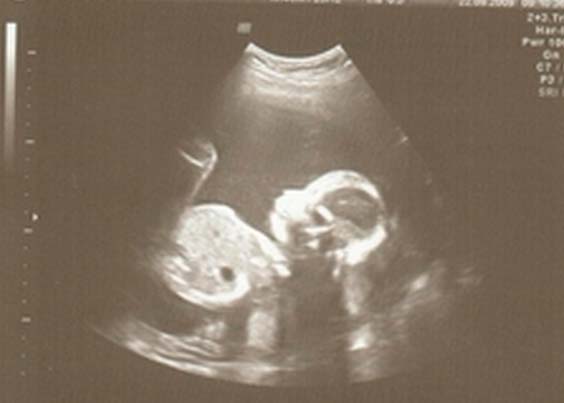

Si vous n'avez pas subi d'échographie, le médecin vous prescrira probablement une référence. Au cours de l'étude, le médecin vérifiera les paramètres physiques du fœtus, vérifiera avec les indicateurs normatifs de la quantité de liquide amniotique, vérifiera l'état du placenta.

Photo échographique à la semaine 22